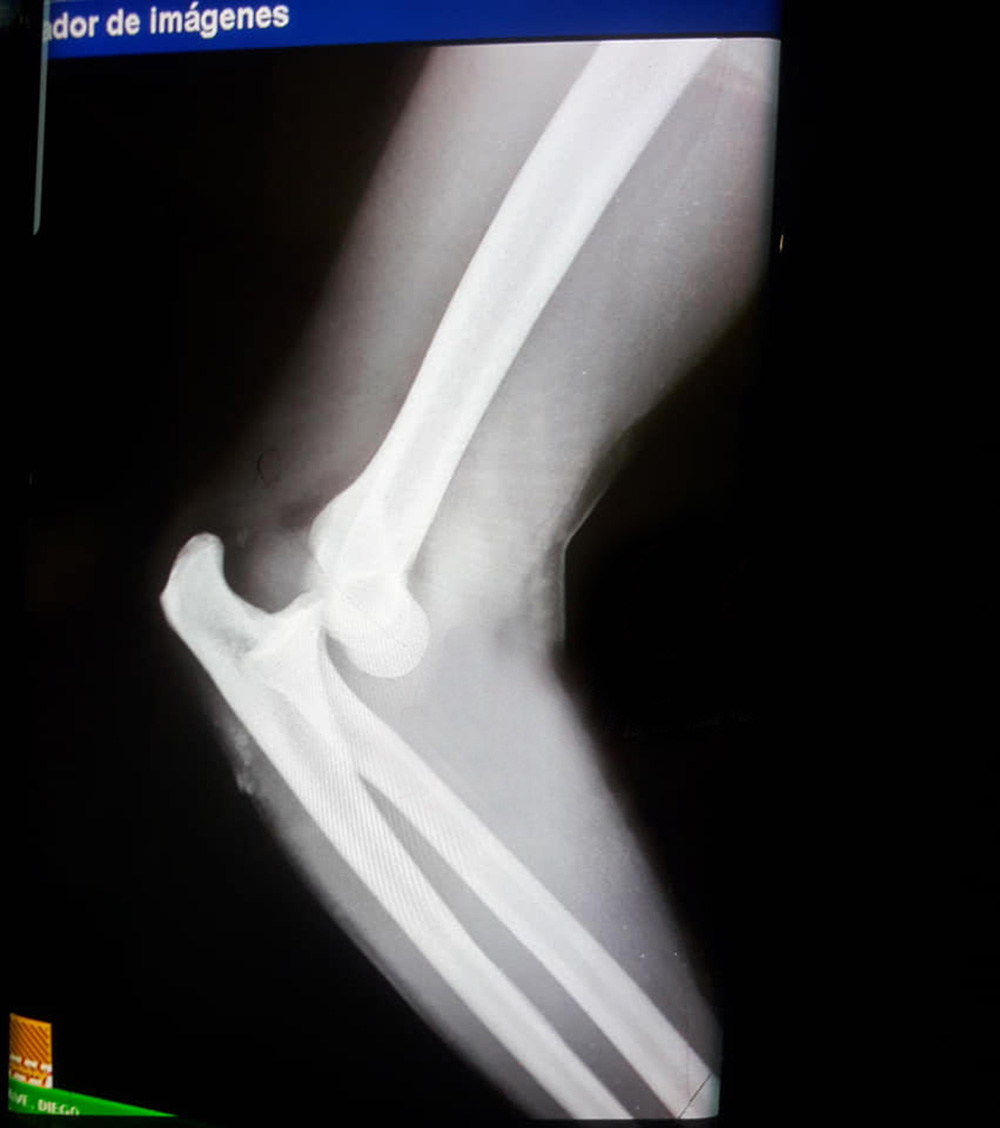

El “uno” franjeado fue trasladado al Hospital Zonal Dr. Camilo Muniagurria y allí se constató que sufrió una luxación posterior en el codo.